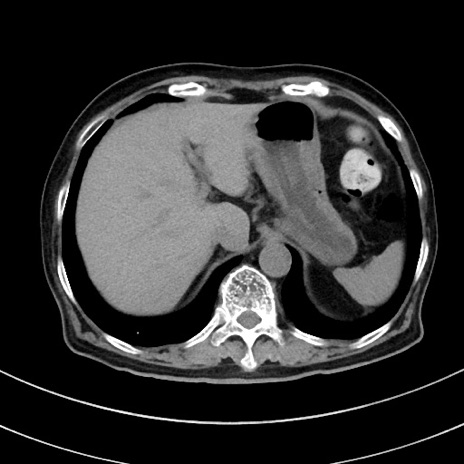

症例33(横断像)

【症例】70歳代 女性

【主訴】心窩部痛

【現病歴】延髄病変の精査・加療にて神経内科入院中。本日より心窩部痛あり。

【既往歴】虫垂炎

【身体所見】右下腹部を中心に圧痛と反跳痛あり。

【データ】WBC 10900、CRP 0.02